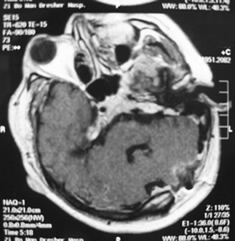

2.CT檢查 CT是目前診斷顱內轉移瘤的首選檢查手段,不僅在大多數情況下能發現腦轉移瘤,還能顯示轉移瘤的形狀大小、部位、數目、伴隨腦水腫及繼發腦積水和中線結構移位程度。CT顯示轉移瘤大多位於皮層或皮層下,圓形或類圓形,呈現低密度等密度、高密度或混雜密度。也可是囊性腫塊,囊腔內可有結節,伴有出血時可顯示出高密度區或液平面。若腫瘤生長快,可顯現出腫瘤中心部分的壞死及囊性變。周圍伴有明顯的低密度指狀水腫,鄰近側裂池或腦池受壓變小或消失,同側側腦室受壓變形、移位,移位明顯者可造成腦幹周圍池部分或全部消失此時患者病情常常很嚴重。強化後可顯示腫瘤呈環狀均勻或團塊狀強化,強化明顯者常提示腫瘤血供豐富,出血明顯者可掩蓋原有徵象易與腦出血混淆。環狀強化者可與腦膿腫混淆。位於顱後窩者常引起較明顯的梗阻性腦積水,四腦室受壓移位明顯,顱後窩特別是接近顱底病變由於偽影的影響常不易顯示,只能根據間接徵象推斷。丘腦及腦幹的轉移瘤常無明顯的腦水腫。水腫的程度與腫瘤惡性程度無明顯關係。CT骨窗位可清楚顯示顱骨受累情況。硬腦膜外轉移者,可見沿顱板下呈梭形或新月形高密度等密度病變。瀰漫型轉移者可見基底池、橋小腦角池等部位高密度影。

另外,不同病理類型的轉移瘤有其特有的CT表現。如肺腺癌和小細胞未分化癌轉移通常為高密度結節或環狀病變,有均一強化,水腫明顯。鱗癌通常為類圓形低密度腫塊,並有薄的環狀強化半數為單發。

3.MRI檢查 MRI檢查不僅能進一步提供轉移瘤的影像學固有特點還能發現多個病變而易於診斷。因為MRI比CT能發現更小的腫瘤,且多發性病灶為轉移瘤的特點。對於顱後窩及近顱底的病變由於去除了骨質的偽影而易於檢出。典型的轉移瘤表現為長T1、長T2信號,周邊有更長信號的水腫帶由於T2加權像上水腫常呈明顯長T2信號,因此比T1加權像更易於發現病變,特別是易於發現較小的病變。有些具特徵性的轉移瘤的T2加權像上可表現為等信號或略低信號。MRI可清楚顯示轉移瘤鄰近的腦回及重要結構受累情況有助於指導手術入路,瘤內有出血者可顯示出不同時期出血的特有MRI表現由於血-腦脊液屏障的破壞,轉移瘤可表現為明顯強化。對瀰漫型引起腦膜轉移者可清楚地看出腦膜的增厚而易於檢出。